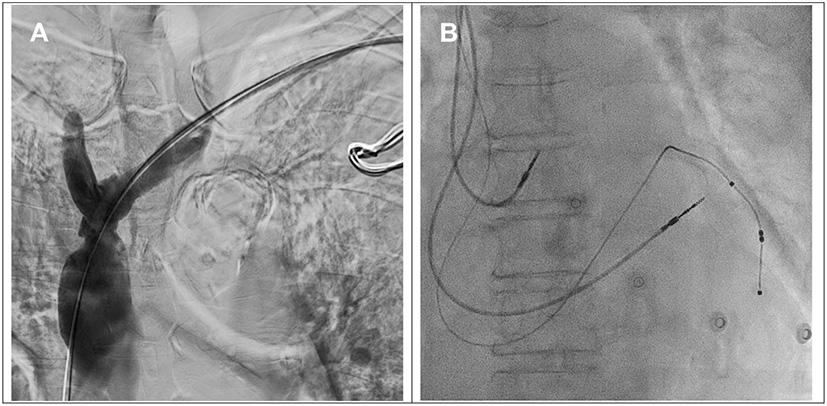

She was diagnosed with right breast cancer 14 years ago in 2008 and underwent neoadjuvant chemotherapy and modified radical mastectomy, followed by adjuvant radiotherapy with 5,000 cGY and hormone therapy with letrozole for 2 years. A Port-a-Cath was implanted via her left subclavian vein (SCV) in 2008 and was removed in 2014. The preprocedural venogram showed partial stenosis in the proximal left SCV, severe stenosis in brachiocephalic vein and Standford type III SVC occlusion (4) (Figure 1A). The SVC chronic complete occlusion was compensated by collateral flow and thus prevented this patient from clinical symptoms.

Figure 1. (A) Venography via the left upper arm demonstrated total occlusion from the brachiocephalic vein (white arrow) to the superior vena cava (SVC) (arrowhead) with abundant collaterals. Left subclavian vein (♦). (B) TERUMO GLIDEWIRE® () with support of a Mustang balloon (3.0 × 40 mm) failed to cross the junction of the brachiocephalic vein and SVC. (C) TERUMO GLIDEWIRE® (⋆) with the support of a multipurpose catheter was advanced to the left internal jugular vein. The antegrade Hi-Torque Connect™ guidewire was successfully advanced to the inferior vena cava. (D) A Mustang balloon (12.0 × 80 mm) was used to dilate the SVC and brachiocephalic vein with 6 atm.

We performed a balloon venoplasty and biventricular pacing CRT(BiV-CRT) implantation with the assistance of a vascular interventionist. We inserted a 6-French (Fr) Merit sheath via the left SCV. With the support of a Mustang balloon (3.0 × 40 mm), we passed a 0.035-inch TERUMO GLIDEWIRE® through the stenotic lesion of the left SCV and the brachiocephalic vein but could not cross the SVC total occlusion (Figure 1B). We escalated the wire to a 0.018-inch Hi-Torque Connect™ wire (Figure 1C) but we still failed to pass it through the lesion. Thus, we used right femoral venous access with an 8-Fr Cordis sheath. With the support of a 6-Fr Multipurpose (MP-1) catheter, the TERUMO GLIDEWIRE® was advanced to left IJV. Under the guidance of the retrograde guidewire, the antegrade Hi-Torque Connect™ wire crossed the SVC total occlusion and was advanced to the inferior vena cava (Figure 1C). A Mustang balloon (3.0 × 40 mm) and a Mustang balloon (12.0 × 80 mm) were used to dilate the brachiocephalic vein and the SVC sequentially (Figure 1D). The post-dilation angiogram revealed patent flow (Figure 2A).